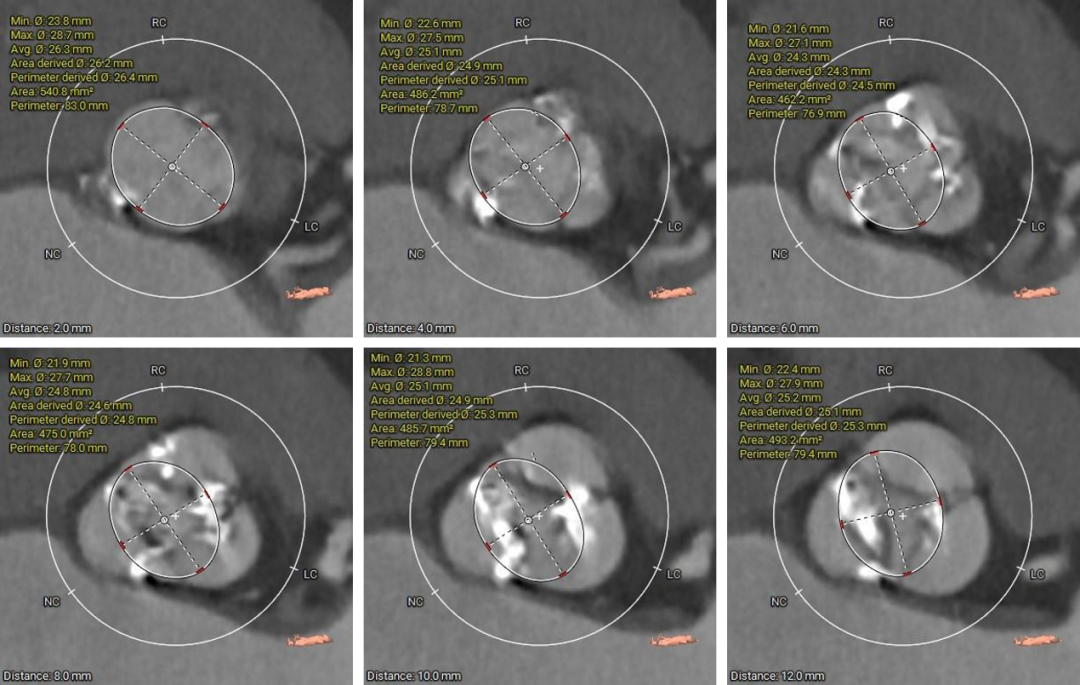

瓣上结构测量

3.瓦氏窦、窦管交界、升主动脉内径尚可;